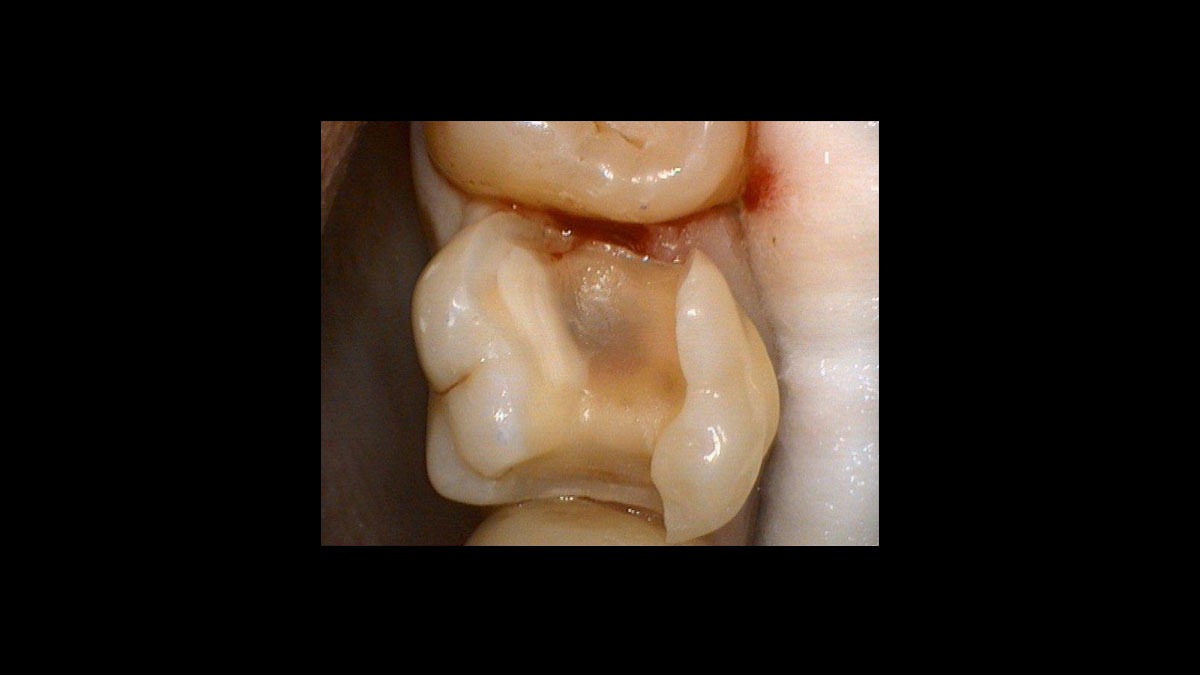

Periodoncia

Las siguientes aplicaciones se presentan en los videos y las imágenes:

• Reducción de gérmenes en periodoncia

Reducción de gérmenes en periodoncia